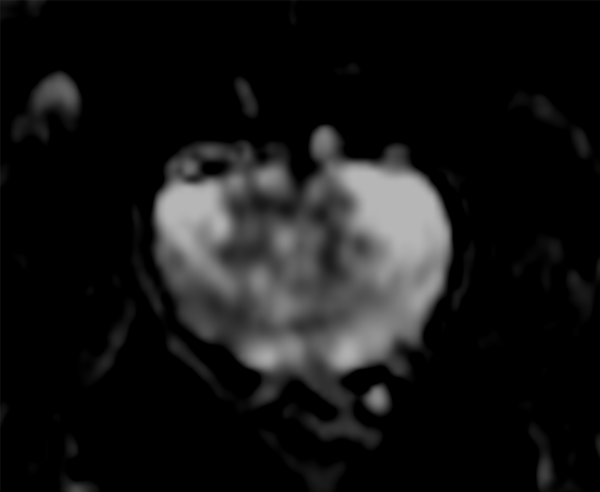

Motion-free Prostate imaging